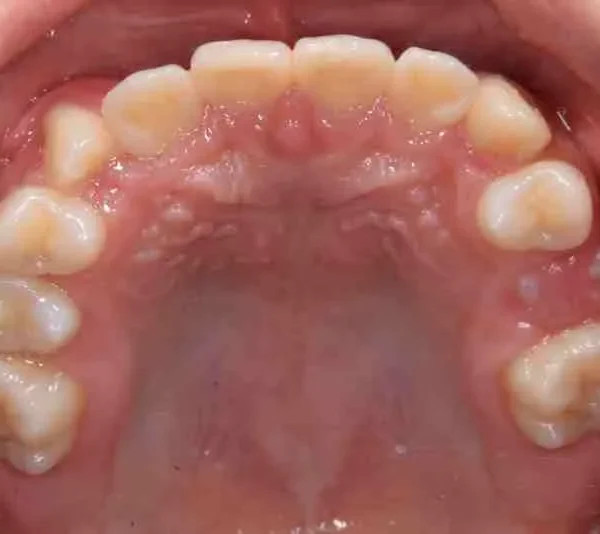

• 治療終了後

治療終了後

先ずは萌出スペースを確保してから開窓術を行い、犬歯を正しい方向へ誘導しました。

マルチブラケット装置は使わずに、最低限の必要な装置を使って目立たないように治療しました。

治療回数29回、2年10ヶ月の治療期間で矯正治療を終了しました。

主訴が改善され、ご満足頂きました。